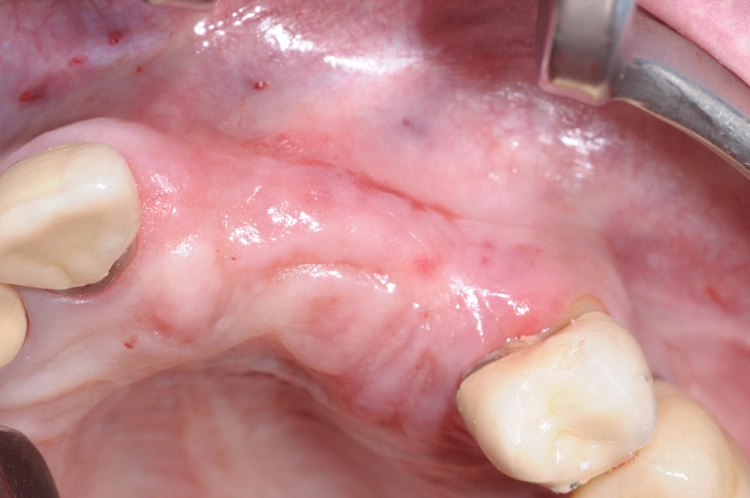

Ein 64 Jahre alter männlicher Patient ohne anamnestische Auffälligkeiten wurde mit dem Wunsch nach einer festsitzenden und ästhetisch ansprechenden Lösung im Frontzahnbereich von seinem Hauszahnarzt zur weiteren implantologischen Rehabilitation an unsere Praxis überwiesen. Nach eingehender klinischer Untersuchung wurde anhand einer 3D-Röntgenaufnahme mittels DVT das knöcherne Lager in der zu behandelnden Region beurteilt, worauf sich ein ausgeprägtes horizontales Knochendefizit zeigte, das eine Implantation in korrekter prothetischer Lage nicht zuließ (Abb. 1-3).

Die Entscheidung fiel daraufhin auf ein zweizeitiges Vorgehen mit vorheriger Knochenaugmentation in Schalentechnik und späterer Implantation von zwei BLT-Implantaten mit augmentativem Relining: Der Patient entschied sich nach ausführlicher Beratung und Vorstellung der alternativen Augmentationsmöglichkeiten für die Schalentechnik mit allogenen Kortikalisplatten und Granulaten (maxgraft® spongiosa, Straumann), wie die Abbildungen 4 bis 7 dokumentieren.